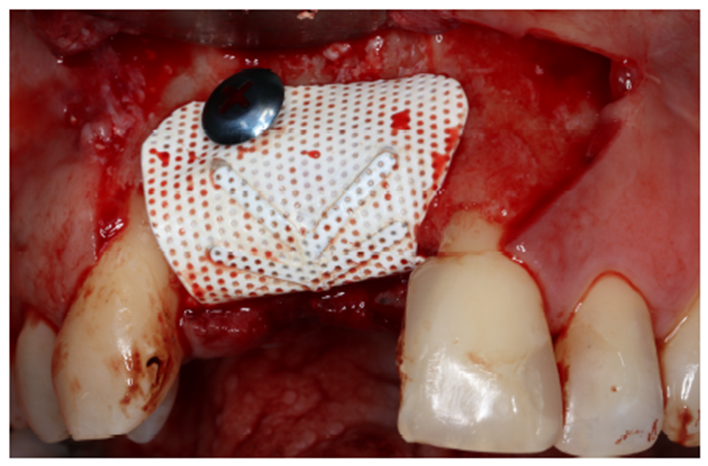

Após a estabilização do enxerto ósseo é recomendável a retenção vestibular das membranas com parafusos de fixação. É importante manter o sítio cirúrgico sem grandes pressões ou movimentações, respeitando os princípios básicos para o sucesso do enxerto, evitando a formação de fibrose. A escolha do parafuso depende da habilidade e preferência do cirurgião. Deve-se sempre ter em mesa o kit de chaves ideal como o parafuso de fixação de escolha. Neste caso, utilizou-se os parafusos de 12 mm de altura da Maximus.Vale ressaltar que o reforço de titânio viabiliza uma manipulação clinica facilitada e auxilia na proteção do enxerto frente às movimentações e/ou pressões (Figura 8).